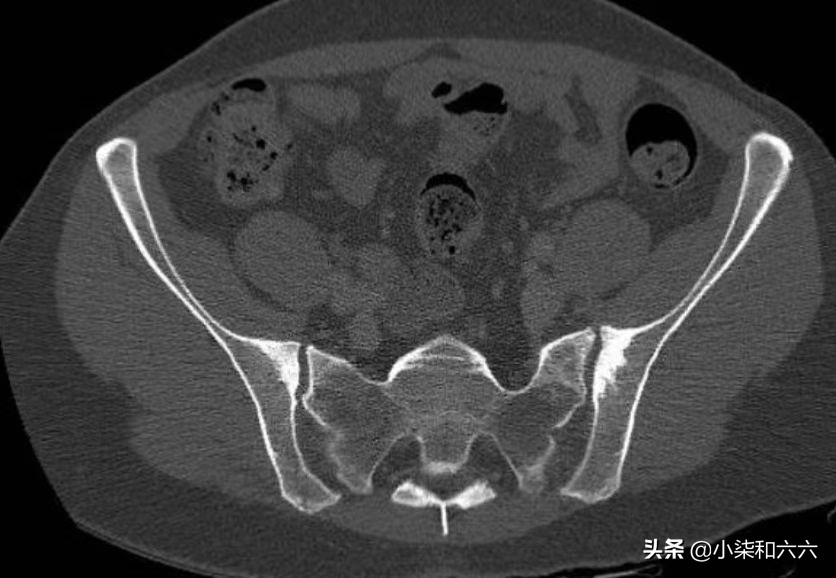

上述箭头所指为骶髂关节

临床上通常以慢性下腰痛或骶髂关节区不适、间歇性酸痛、隐痛为主,多为一侧性,严重者常伴有髋关节活动障碍,且疼痛会向臀部、大腿背侧放射,步行、久坐、久站、负重及劳累后症状会加重。骶髂关节及臀中肌压痛明显,骨盆挤压及分离试验、4字试验阳性。放射学特征为骶髂关节的髂骨侧硬化,通常为双侧、对称和三角形,硬化区轮廓分明且致密,主要位于前中三分之一处。

骶髂关节髂骨侧硬化,骶髂关节间隙正常